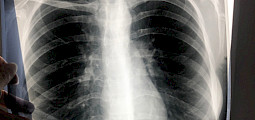

Кыргызстанда бир суткада коронавирус 371 адамдан табылып, 4 бейтап каза болду